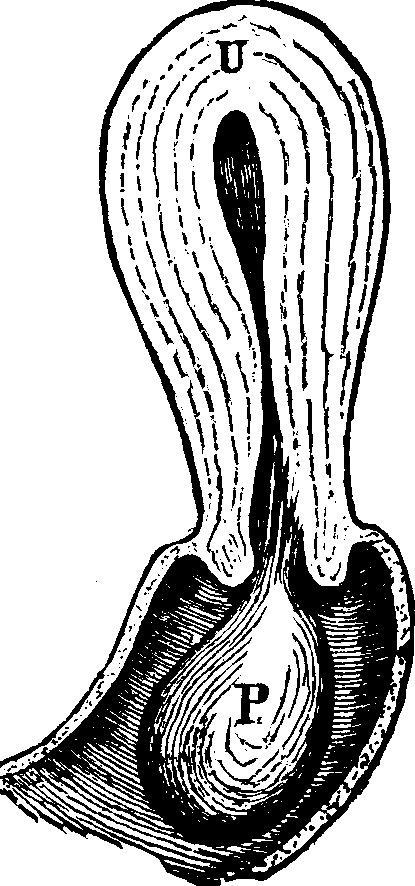

The function of the ovaries is to furnish ova or germs, and the functions of the uterus or womb are to secrete mucus; to exude the menses; to secrete the decidua; to contain and nourish the foetus and to effect its expulsion.

Absence or Malformation of the Womb. The uterus may be deformed or entirely absent, and yet there be an inclination, or symptoms indicative of an effort, to establish this function. The individual may be delicate in organization, graceful in bearing, refined and attractive in all feminine ways, and yet this organ may be so defective as to preclude the establishment of the menstrual function. Sometimes there is merely an occlusion of the mouth of the uterus, the perforation of which removes all difficulty. In others, the neck of the womb is filled with a morbid growth, or the walls of its canal are adherent, as the result of inflammation, and may be separated by a small silver or ivory probe, and the menses be thus liberated.